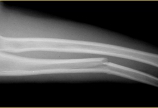

患者,女,10岁,左肘畸形5年。家属诉5岁时左肘跌伤,经乡医治疗。10岁来院诊治,目前肘外翻畸形,屈曲功能良好,伸直约120°。讨论的问题,1.患者是否需要手术治疗?2.若患者需要手术治疗,那么手术时机该如何选择?为什么?3.若认为可以进行手术治疗,手术的关键点在哪?